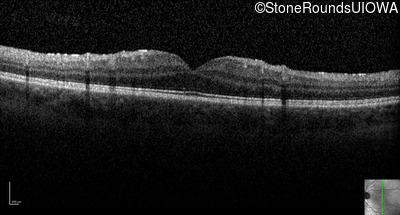

Optical Coherence Tomography - Left - 20/20 -2

Exemplar / OCT Stack